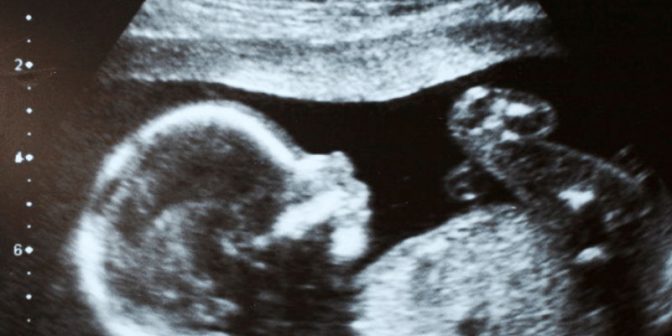

Dokter akan melakukan ultrasound (USG) terhadap janin jika mencurigai adanya polihidramnion pada janin. Jika USG menunjukkan hasil adanya polihidramnion, maka akan dilakukan jenis USG yang lebih detail.

Dokter akan mengukur kantong cairan terbesar dan paling dalam di sekitar bayi untuk memperkirakan jumlah cairan amnion yang ada di dalam rahim. Jika nilai cairan amnion berukuran 8 cm ataupun lebih, maka menunjukkan adanya polihidramnion.

Cara lain yang dapat anda lakukan untuk mengukur cairan amnion yaitu dengan mengukur kantong besar pada empat bagian spesifik dari rahim. Jumlah pengukuran tersebut merupakan indeks cairan amnion (the amniotic fluid index-AFI).

Jika indeks cairan amnion berada pada angka 25 cm ataupun lebih. Hal ini menunjukkan adanya polihidramnion pada janin. Dokter akan menggunakan USG yang lebih detail utuk mendiagnosis maupun menyingkirkan cacat lahir dan komplikasi lainnya.